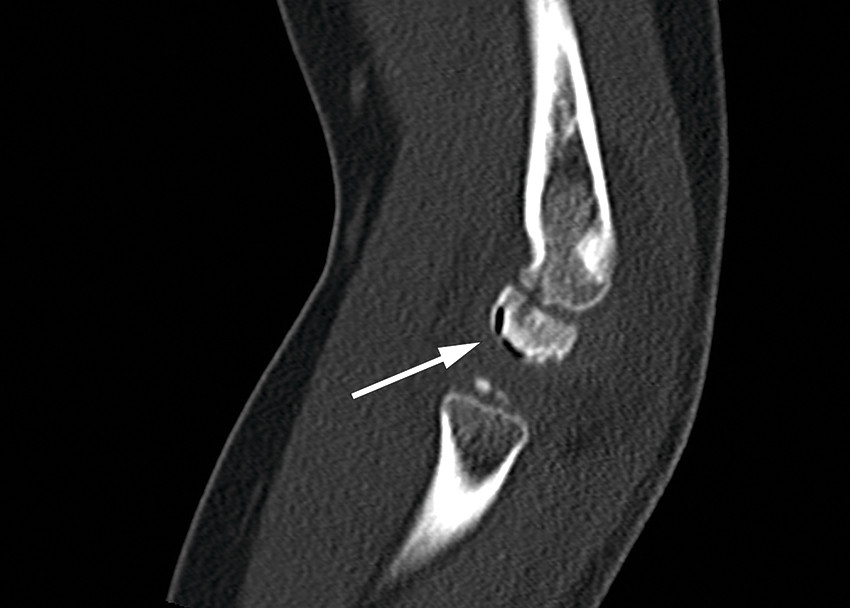

CT scan showing the vacuum phenomenon (white arrow).

Typical clinical findings in Panner's disease are pain, swelling, stiffness and reduced range of motion in the elbow joint. Morphological changes can be seen on X-ray, along with contour deformity, collapse and increased density of the capitulum (1). The subchondral vacuum phenomenon is a rare finding, but is highly specific to this condition. The vacuum phenomenon, which represents subchondral gas formation, is a sign of bone ischaemia and may indicate aseptic necrosis (1).